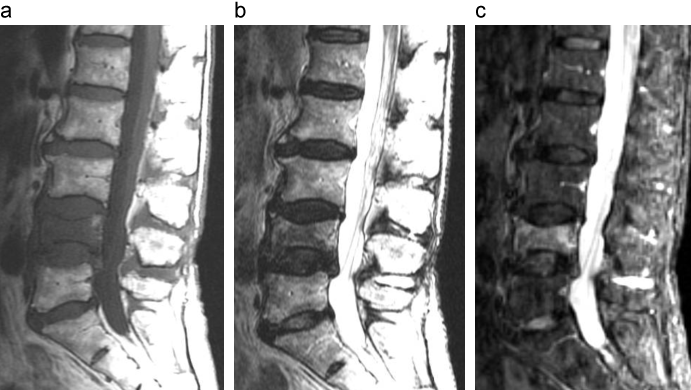

症例2のMRI、CT画像

第1腰椎に信号変化を認める。T1強調画像で低信号、T2強調画像で高信号を示す領域は液体貯留を示し、骨癒合不全を示唆する所見である。

a:MRI T1強調画像

b:MRI T2強調画像

c:CT画像

出典

img

1: 著者提供